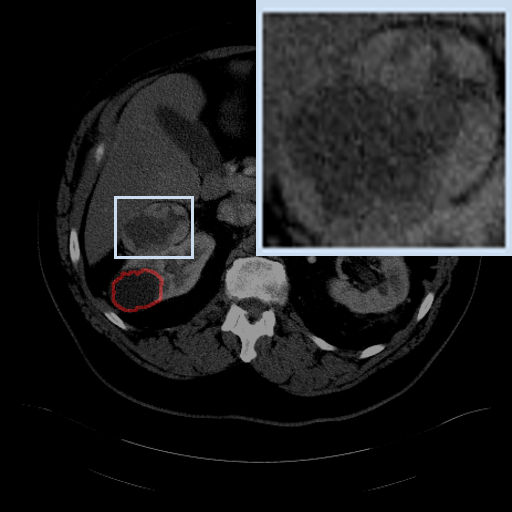

Figure 3: Qualitative comparison visualization of DEAP-3DSAM and baselines on four datasets.

IV-B2 Qualitative Performance Comparison

We also performed qualitative analysis on four datasets. As illustrated in Fig. 3, DEAP-3DSAM accurately identifies the target regions and closely matches their size. In contrast, 3DSAM-Adapter [3dsamadapter] exhibits limitations in matching the size and shape of the target regions. This proves that DEAP-3DSAM captures more complex image features, owing to its Dual Attention Prompter and Feature Enhanced Decoder. Furthermore, while these SAM-based methods are nearly capable of localizing the target regions, many traditional methods, i.e. UNETR++ [unetr++], Swin-UNETR [swinunetr], and TransBTS [transbts], struggle to achieve this. This highlights the potential of SAM-based methods for addressing complex 3D segmentation tasks.